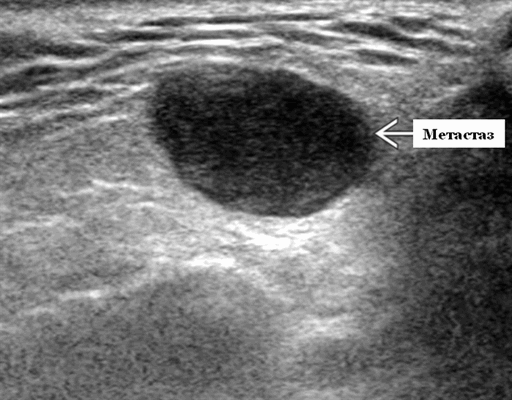

- Одиночные или множественные гипоэхогенные образования при известном распределении внутрипаротидных лимфоузлов.

- На ультразвуковом сканировании образование четко или плохо определено (экстранодальное распространение)

- На УЗИ определяется аномальная внутренняя архитектура ± эхогенные ворота, эхогенность однородная или неоднородная с внутренними кистозными участками в некротических узлах

- ± Метастатические шейные лимфатические узлы

- Интранодулярный кровоток хаотичный / дезорганизованный или преимущественно периферический

- Ультразвуковое сканирование дает оптимальную характеристику лимфоузлов в поверхностной доле и проведение подтверждающей биопсии.

Результаты ультразвукового исследования слюнной железы

Серошкальное УЗИ. Одиночные или множественные гипоэхогенные образования в известном распределении внутрипаротидных лимфоузлов. Хорошо выраженный или слабо окаймленный (экстранодальное распространение). Экстранодальное распространение. Обратите внимание на местную инвазию интрапаротидной наружной сонной артерии (ВСА), ретромандибулярной вены или экстрапаротидных мягких тканей. Аномальная внутренняя архитектура ± эхогенные ворота. Однородный или неоднородный вид с внутренними кистозными участками в некротических узлах ± метастазы в шейные лимфатические узлы